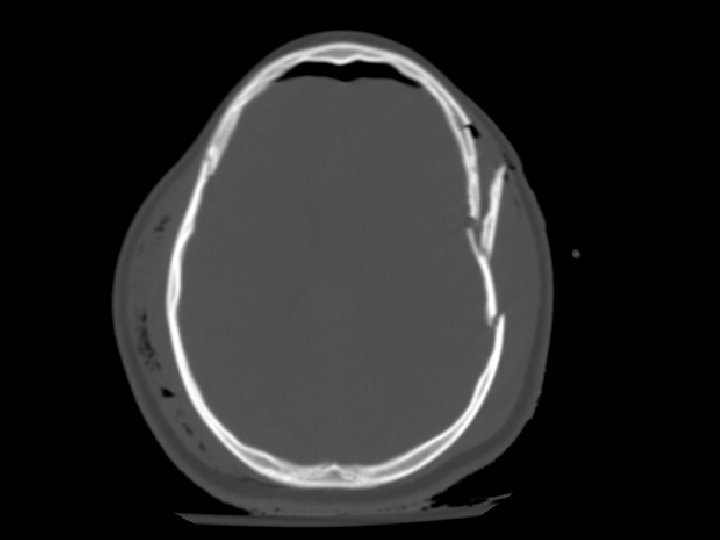

Vỡ xương sọ • Nhiều dạng: – Nứt, lún, rạn nền sọ • Cắt lớp dạng cửa sổ xương • Tổn thương não ở điểm vỡ xương sọ là rất quan trọng • Dường nứt sọ: – Nếu nứt sọ kín, có thể chỉ quan sát theo dõi

Vỡ xương sọ • Vỡ nền sọ: – Thường liên quan đến xương thái dương – Chẩn đoán lâm sàng (CT thường bỏ sót chẩn đoán) • Dấu hiệu đeo kính râm, chảy máu tai, dấu hiệu Battle (tụ máu sau tai), dò nước não tủy qua mũi • Lún sọ: – Phẫu thuật nâng lún: • nếu lớn hơn độ rộng của sọ hoặc • > 5 mm